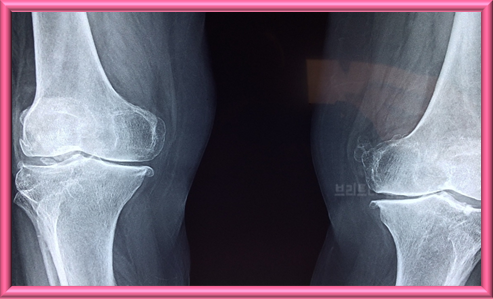

3. 수술적 치료

약물 또는 비약 물 치료에도 증상이 지속하거나 관절 손상이 심한 경우 수술적 치료가 필요할 수 있다.

3.1 관절 치환술

심하게 손상된 관절을 인공관절로 교체하는 수술이다. 주로 무릎, 엉덩이, 어깨 등 관절 부위에 시행된다. 관절 치환 수술은 통증을 완화하고 관절 기능을 향상하며 삶의 질을 크게 향상할 수 있다.